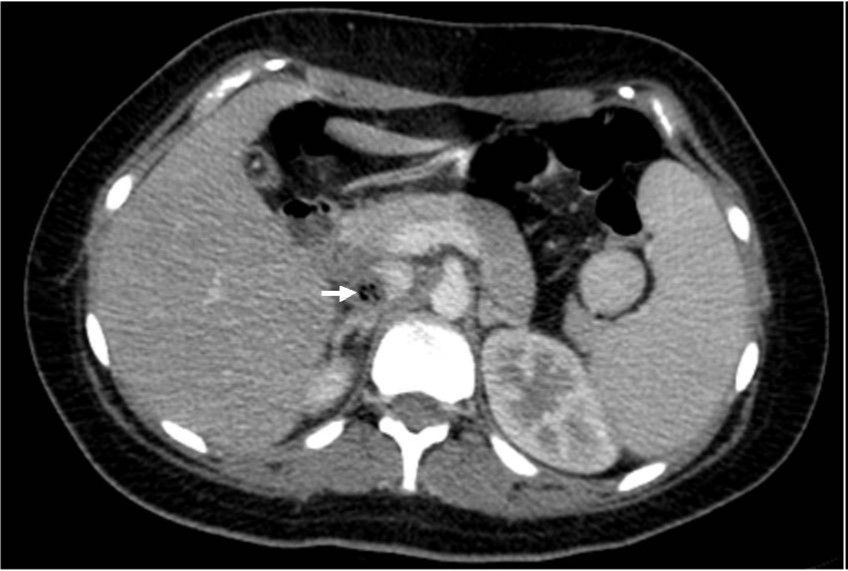

복부 컴퓨터단층촬영에서 12번 흉추골 높이의 하대 정맥에 2.5cm 크기의 공기방울을 포함한 혈전이 있다(Fig. 1A, IB). 하대정맥조영술에서 내경의 50%정도를 채우고 있는 혈전으로 인한 filling defect가 있다 (Fig. 2A). 혈전의 상부에 임시 하대정맥 필터로 Niti-S 스텐트를 삽입한 후 부분적으로(50%) 펼쳤다(Fig. 2B). Renal guiding catheter를 삽입하여 혈전에 대해 수차례 흡인 혈전제거술을 시행하여 다량의 백색혈전을 흡인하였다(Fig. 2C). 이후 시행한 하대정맥조영술에서 혈전의 일부가 스텐트 내부로 이동한 것을 확인하고 스텐트를 재포획하여 혈전을 제거하였다 (Fig. 2D). 스텐트에 혈전 및 나무재질의 이쑤시개가 배출되었다 (Fig. 3A, 3B).

Fig. 2. A

Fig. 2. A. IVC venogram shows large filling defect due to thrombus.

Fig. 2. B

B. Radiography obtained during partial deployment of stent as a temporary IVC filter.

Fig. 2. C

C. Radiography obtained during aspiration thrombectomy of IVC thrombus by renal guiding catheter.

Fig. 2. D

D. IVC venogram after aspiration thrombectomy shows migrated thrombus entrapped in the partially deployed stent.